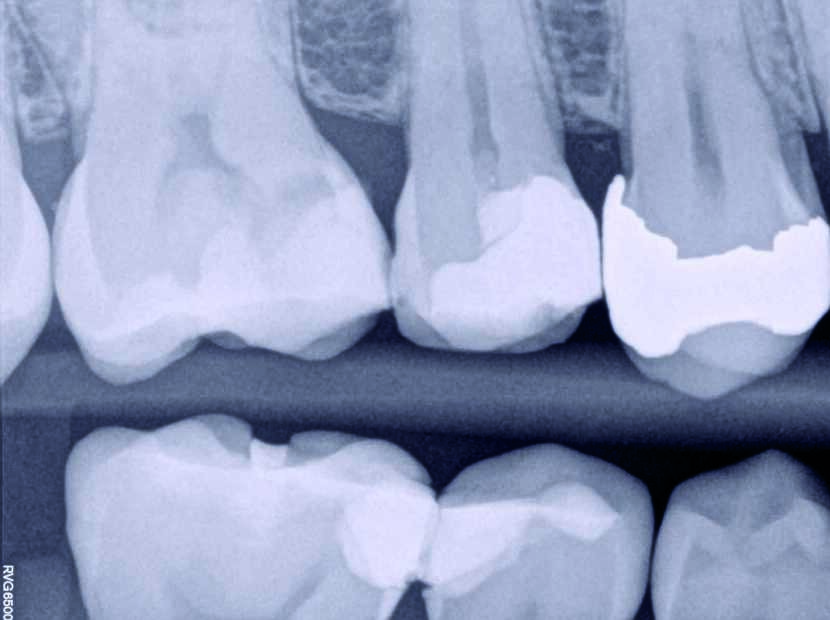

Ein 35-jähriger Patient kam mit vorübergehenden, provozierten Zahnschmerzen an Zahn #4 in die Zahnklinik. Die Diagnose lautete reversible Pulpitis. Es wurde dasselbe Behandlungsprotokoll zum Erhalt der Pulpenvitalität wie im klinischen Fall 1 eingehalten (Abb. 10, 11 und 12), nur dass in diesem Fall die endgültige Zahnreparatur nicht während derselben Sitzung erfolgte. Stattdessen wurde ein vorübergehendes strahlendurchlässiges Reparaturmaterial eingesetzt. Damit konnte die richtige Dicke des Materials für die Pulpa-Überkappung und seine korrekte Positionierung auf der Höhe des Lochs gewährleistet werden, während der Zahnrand für ein gutes Klebeprotokoll sauber gehalten wurde (Abb. 13, 14 und 15). Es wurde berichtet, dass die Erfolgsrate bei den Behandlungsverfahren zum Erhalt der Pulpenvitalität abfallen kann, wenn die endgültige Zahnreparatur zwei Tage nach dem ursprünglichen Verfahren durchgeführt wird. (8) Das MAP-System ist äußerst hilfreich im Hinblick auf eine präzise und stabile Platzierung des Überkappungsmaterials bei unmittelbaren und mittelbaren Verfahren sowie bei partiellen und vollständigen Pulpotomien. In diesem Fall erfolgte die abschliessende Reparatur 15 Tage nach dem ursprünglichen Verfahren und der Patient war vollständig symptomfrei. Neun Monate später wurde die vollständige Bildung des Kalkgewebes auf der Höhe der Pulpen-Überkappung festgestellt, der Zahn ist vital geblieben und der Patient ist vollständig symptomfrei (Abb. 16).